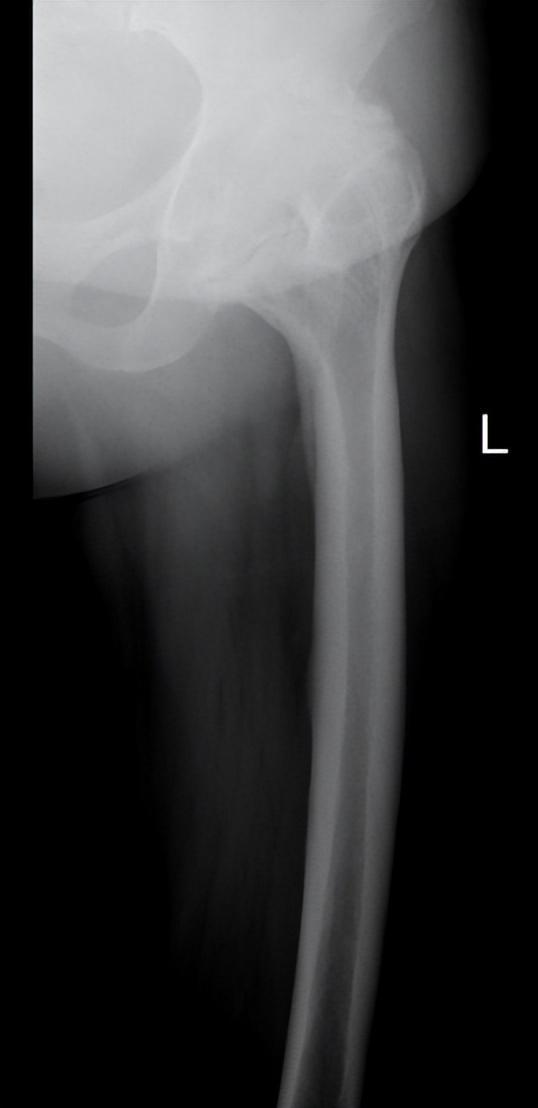

▲患者术前术后影像资料

患者十多岁时左侧髋部受过一次伤未引起重视。由于没有经过及时和正规的治疗,患者髋关节外伤引起的创伤性关节炎致关节软骨退化变性和继发软骨增生、骨化,髋臼大量骨赘增生导致髋关节无法活动,慢慢的股骨头和髋臼的骨头长到一起,最终形成两者的骨性融合,使髋关节失去了原有的功能,平时活动只能靠腰椎,膝关节来代偿勉强完成日常的活动和劳作。